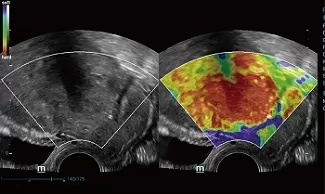

O υπερηχογράφος DC-60 του κατασκευαστικού οίκου Mindray:

Ο έγχρωμος υπερηχογράφος DC-60 μοντέρνου σχεδιασμού με προγραμματιζόμενη οθόνη αφής 10,4′ προσφέρει ποιότητα απεικόνισης σε ένα ευρύ φάσμα κλινικών εφαρμογών. Η υψηλή ταχύτητα επεξεργασίας και τα πρωτόκολλα αυτοματοποιημένων μετρήσεων μειώνουν τον χρόνο σάρωσης και αυξάνουν την εύρυθμη λειτουργία ενός ιατρείου.